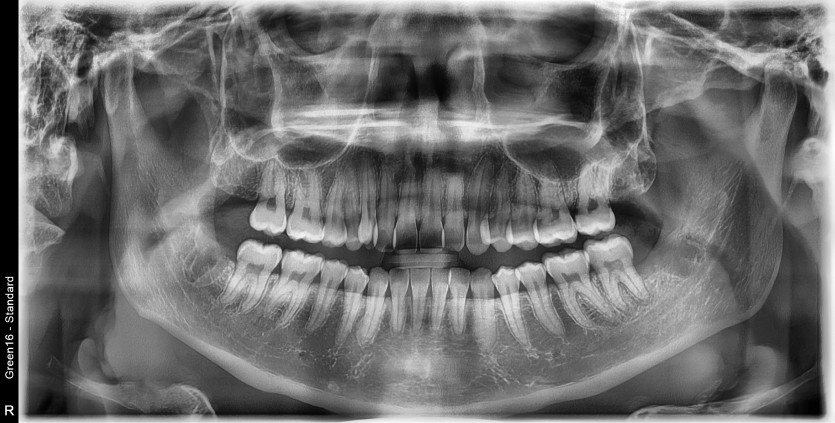

#28,38,48 사랑니 발치

구강 외과 전문의가 당일 발치했습니다.